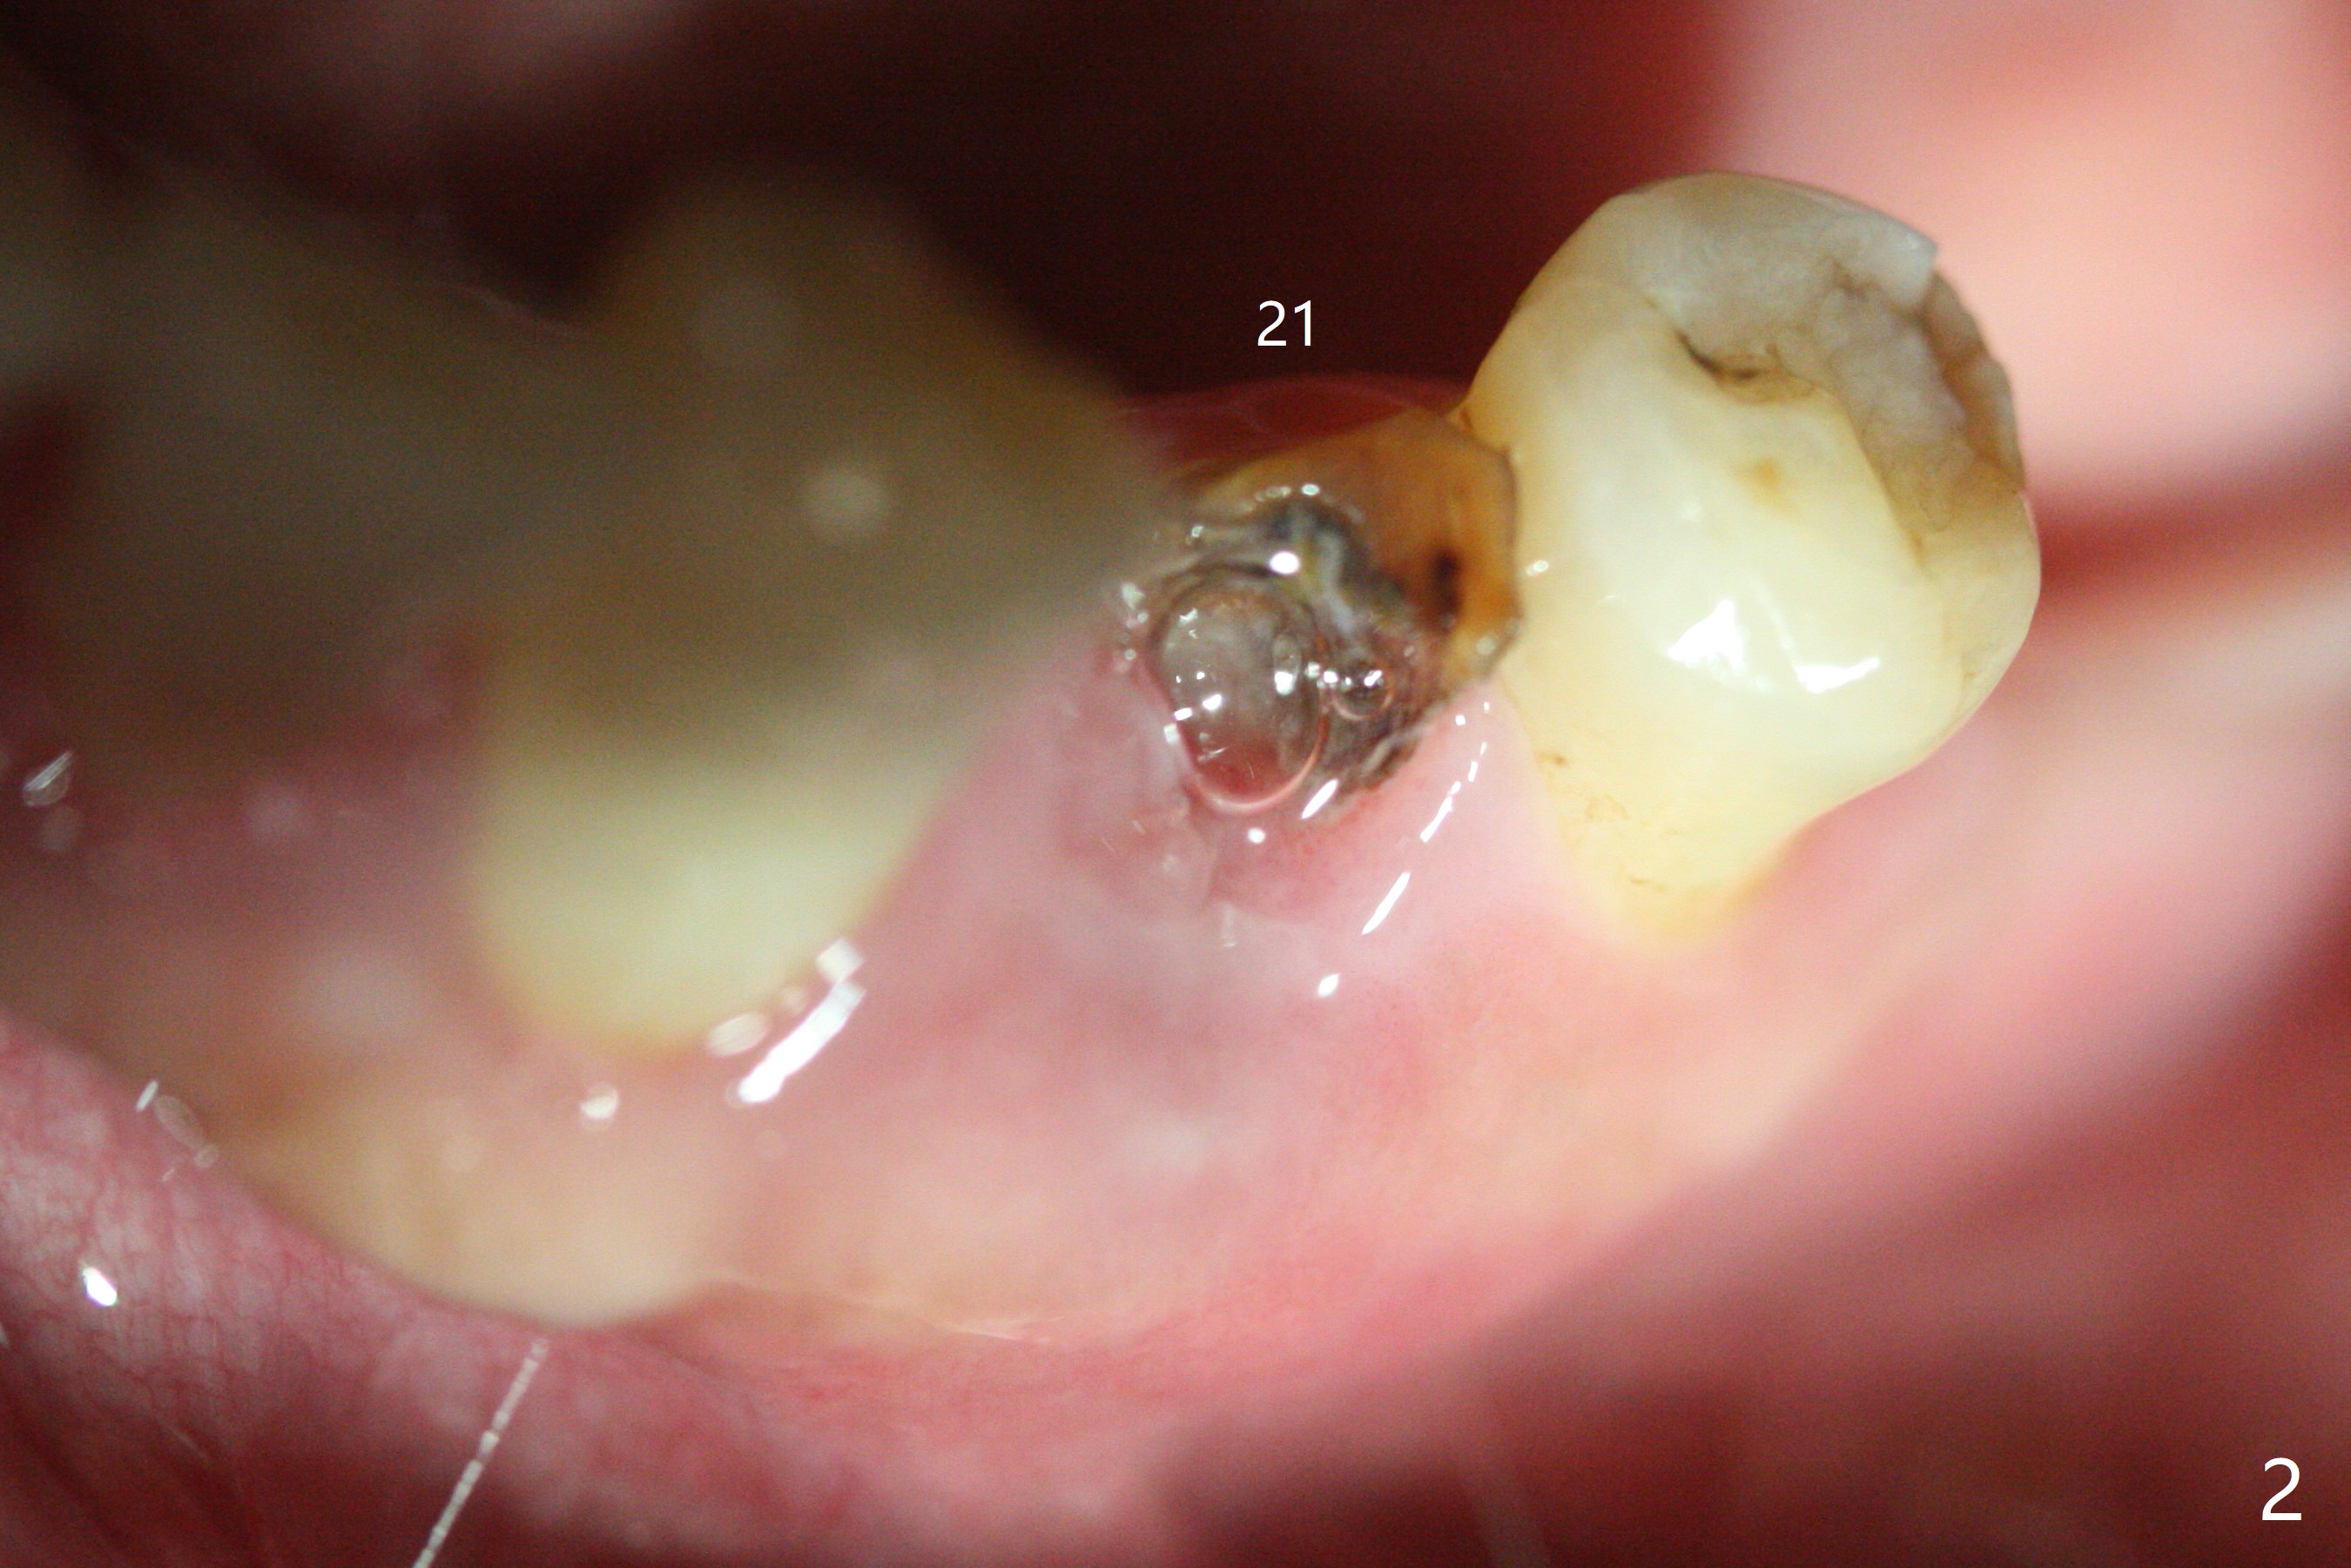

Since the root surface at #29 is distinct (Fig.1), while that at #21 is not (with subgingival caries, Fig.2), closed and open socket shields are done at #29 and 21, respectively (Fig.3,4 S), followed by implant placement with guide (Fig.4-6). With socket shield, there is limited remaining space for bone graft (Fig.4). The shield associated with the closed technique is exposed nearly 2 months postop (Fig.7), while the one associated with the open technique is not (Fig.8). The buccal plate is minimally atrophic with either technique.